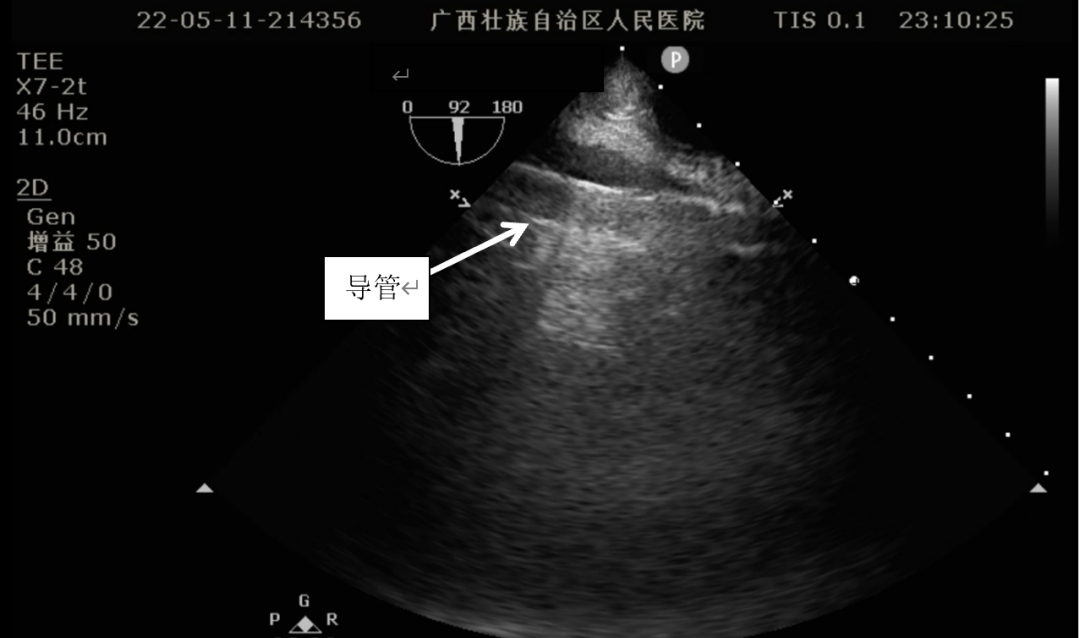

食道超声引导下进行Crescent置管及定位:

食道超声定位导管